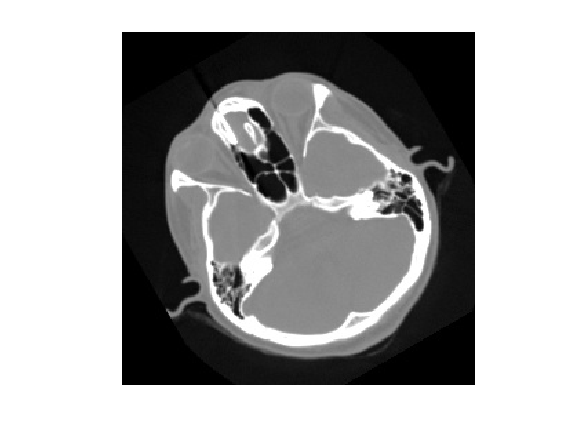

imshow(pixels, [0, 255])

imshow(pixels)